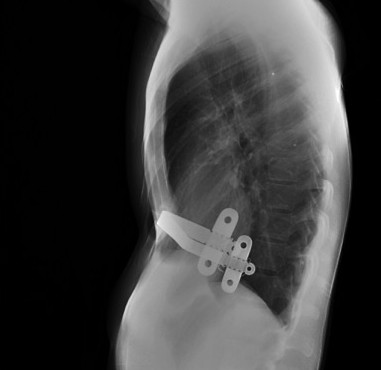

El diagnóstico es clínico. Con la imagen evaluamos mejor la deformidad, útil en caso de ser necesaria la cirugía.

En la Rx de tórax se observa el borramiento del borde cardiaco derecho y en la placa lateral, la depresión interna del esternón, característicamente del cuerpo esternal y de la apófisis xifoides. En casos más acentuados, el corazón, los pulmones, el esófago y el diafragma pueden estar comprimidos, con desplazamiento del corazón hacia la izquierda y prominencia del tronco de la arteria pulmonar en la proyección PA; hallazgos mas evidentes gracias al TC y las reconstrucciones.

Índice de Haller:

- Medio: 3,2

- Moderado: 3,2-3,5

- Severo: > 3,5 (cirugía).